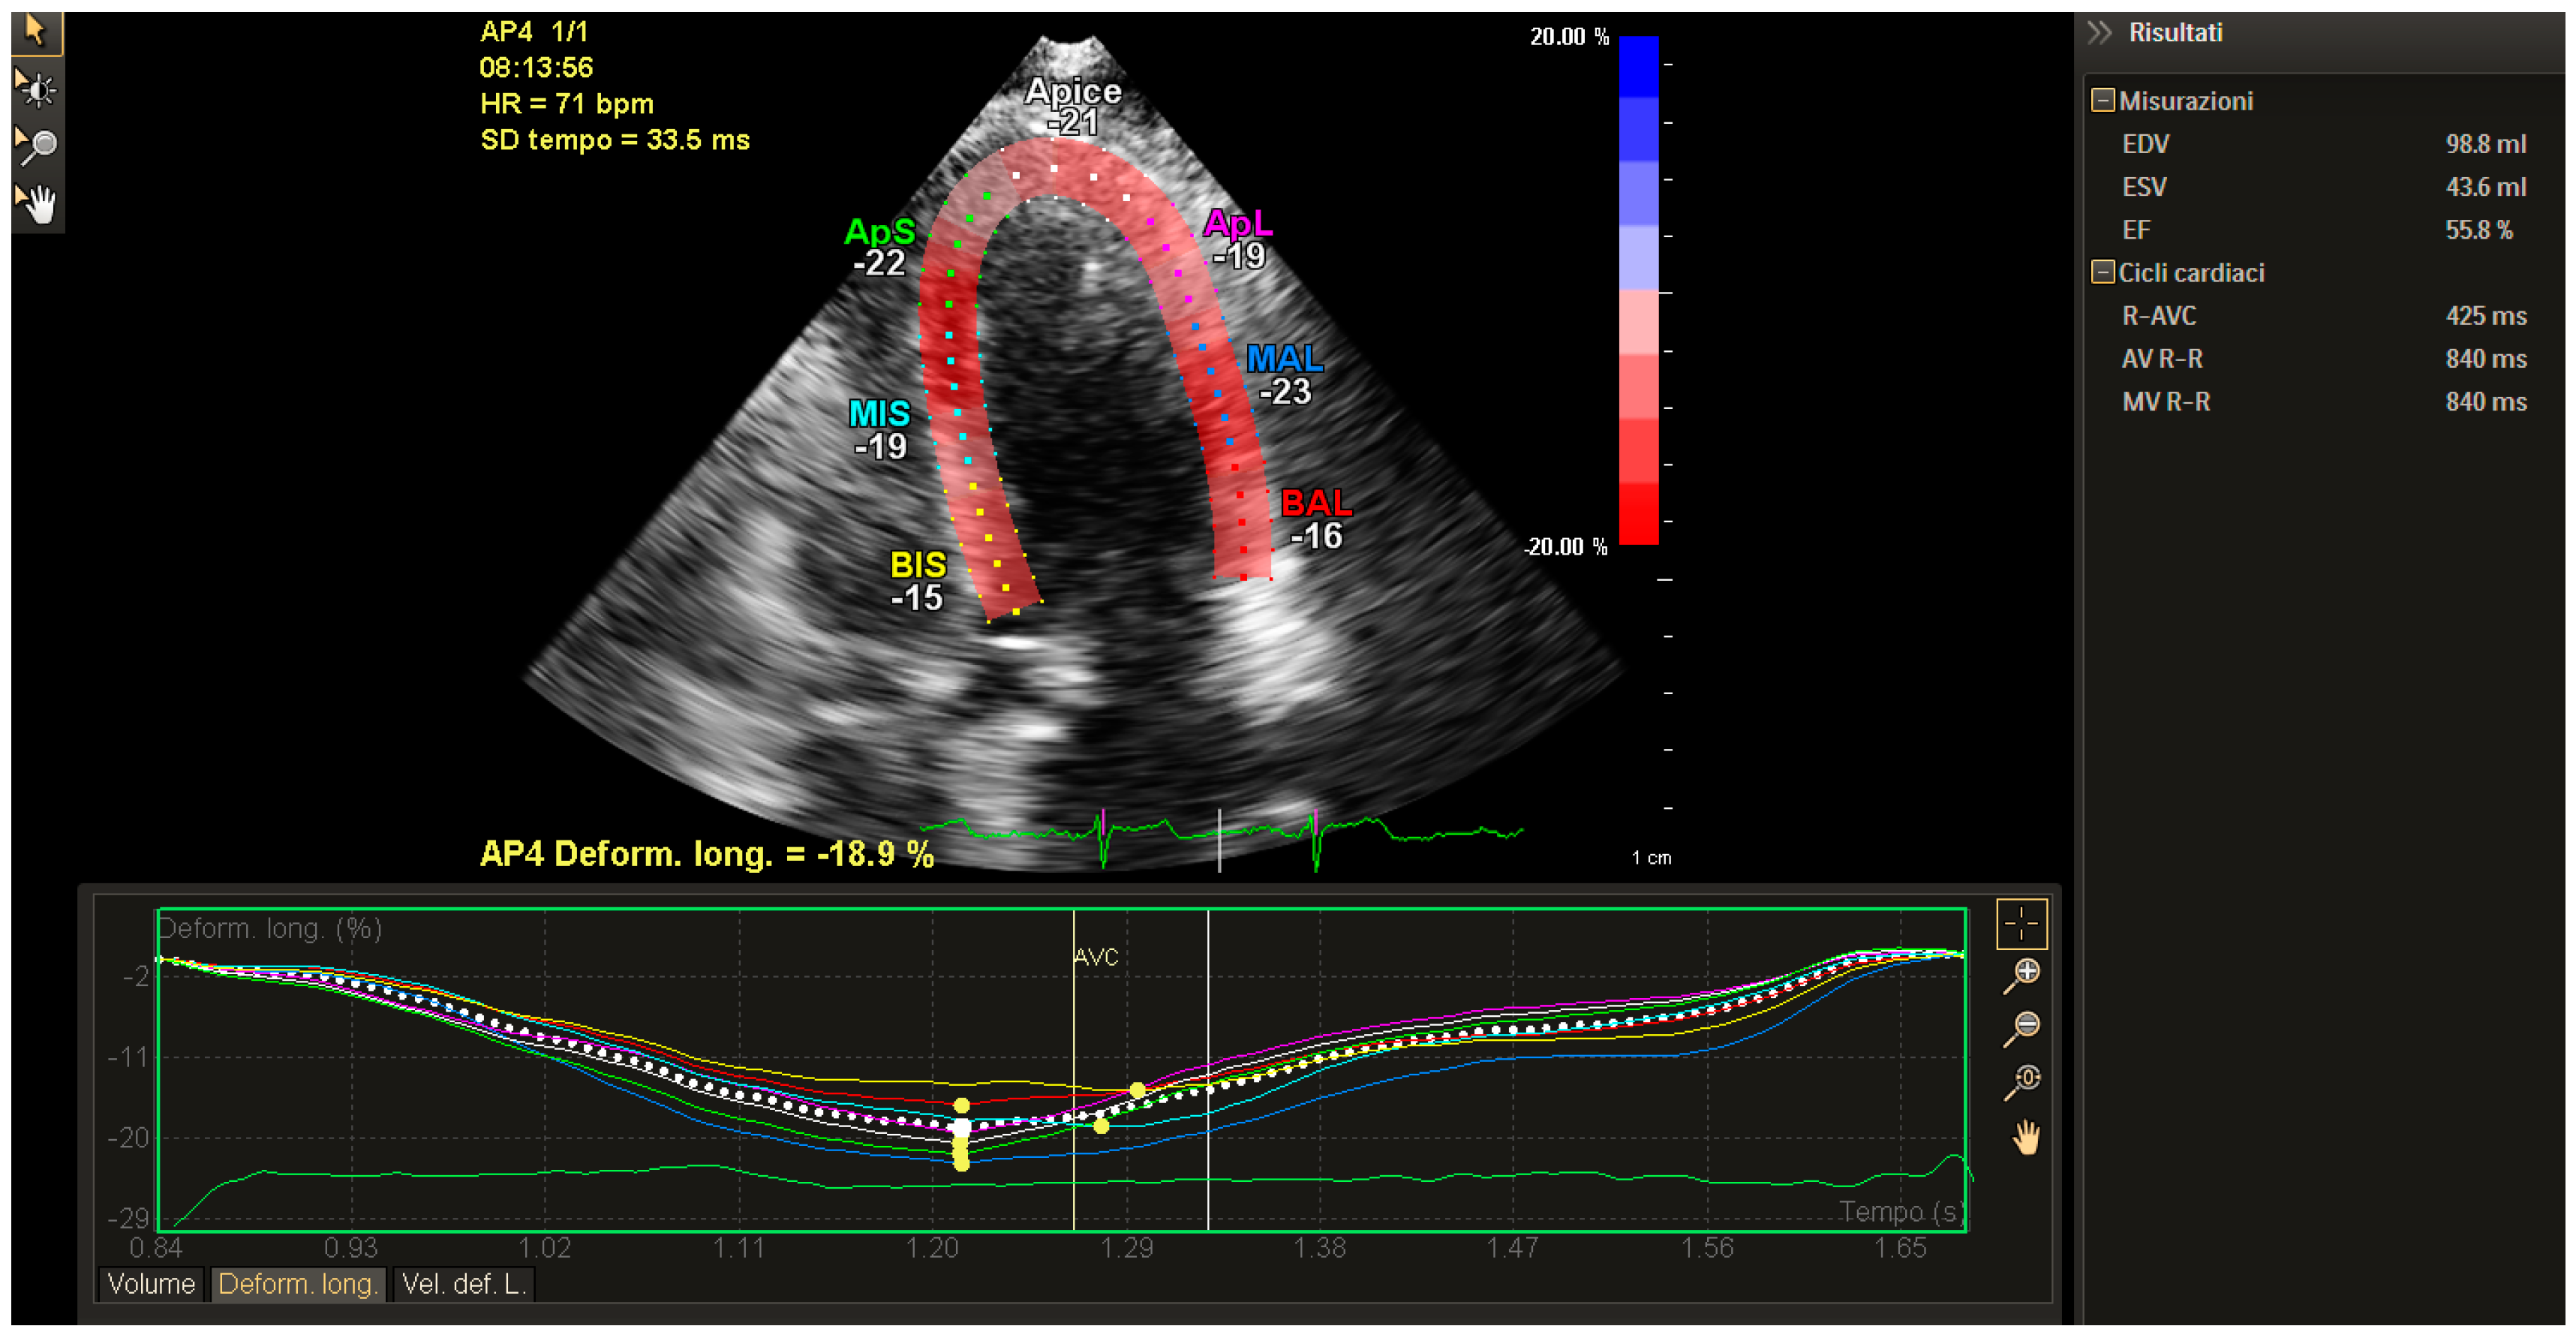

The correct image acquisition for the longitudinal strain is normally performed from the apical 2C, 3C and 4C views; with the eventual global value computed by their average. For a correct acquisition at rest condition, it is also important to adjust frame rate >40 fps or to modify up to 100 fps in case of exercise. The measures need to be repeated at least 3–4 time for reliable results. The normal value of systolic longitudinal strain ranges around −20% corresponding to the shortening of wall length of at least 10 mm, in large part represented by the upward excursion of the mitral valvular plane. As an example, some figures regarding the post processing analysis from two different software packages (ESAOTE, Genova, Italy; and Philips, Andover, MA, USA) have been shown (Figure 1, Figure 2, Figure 3 and Figure 4).

Figure 1.

Global Longitudinal Strain (GLS) of left ventricle (LV) (from a four-chamber view) in a breast cancer patient under chemotherapy and treated by exercise as prescription therapy at moderate intensity. The values have been calculated by the using the iE33Philips echocardiographydedicated Strain (5X-1/Strain) software from the apex view. The figure shows the mean (dotted line) and the segmental values of the profile of the longitudinal strain analysis. The strain values have been obtained by the post processing analysis performed by X-Strain software (Q-station) included in the Philips echocardiography. The EF (ejection fraction) value (55%) is at the lower level of the normal range and in agreement with the data of longitudinal strain (−18.9%) data. With respect to the AVC (Aortic valve closure) marker there is evidence of a PSP (Post Systolic Peck) value.